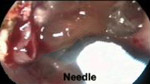

手術圖例-耳鼻喉科手術圖例

• EE229A使用圖例EE229A使用圖例